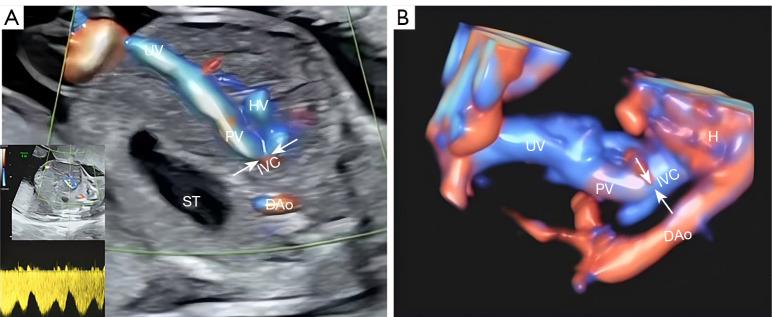

Fetuses with umbilical-portal-systemic venous shunt (UPSVS) have poor prognosis, and standard prenatal ultrasound planes do not contain the umbilical-portal-systemic venous system. Moreover, UPSVS-related research is limited, and the rate of chromosomal abnormalities remains unknown. It is necessary to further clarify the ultrasound characteristics and prognosis of these fetuses and develop effective diagnostic models. Accordingly, the objective of this study was to examine the ultrasound image characteristics of fetuses with different types of UPSVS using two-dimensional ultrasound combined with spatiotemporal correlation imaging technology (STIC) and analyzed the chromosomal abnormality rate and pregnancy outcomes.

The combination of two-dimensional ultrasound and STIC provides reliable evidence for the diagnosis of UPSVS. Types of UPSVS and chromosomal (or genetic) abnormalities affect the prognosis of UPSVS fetuses.

患有脐门静脉-体静脉分流(UPSVS)的胎儿预后较差,而标准产前超声切面不包含脐门静脉-体静脉系统。此外,与UPSVS相关的研究有限,染色体异常的发生率仍然未知。有必要进一步阐明这些胎儿的超声特征和预后,并开发有效的诊断模型。因此,本研究的目的是使用二维超声结合时空关联成像技术(STIC)检查不同类型UPSVS胎儿的超声图像特征,并分析染色体异常率和妊娠结局。

二维超声与STIC相结合为UPSVS的诊断提供了可靠依据。UPSVS的类型和染色体(或基因)异常影响UPSVS胎儿的预后。